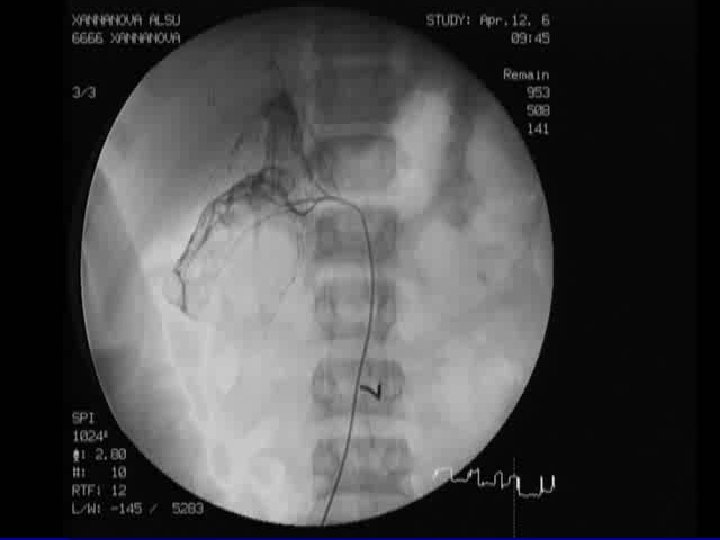

n n n КТ почек (от 16. 02. 06) Заключение: 2 -х сторонний гидронефроз. МЦУГ (23. 06) Заключение: пузырномочеточникового рефлюкса нет. Уретра без инфравезикальной обструкции. Ангиография почек (12. 04. 06) Заключение: дисплазия основных стволов и внутриорганных ветвей обеих почечных артерий, с тотальной атрофией почечной паренхимы (справа 66% от N, слева 62 % от N) 11 марта 2007 года проводиться операция уретеронефрэктомия справа. Масса удаленной почки 6 грамм.

n n n КТ почек (от 16. 02. 06) Заключение: 2 -х сторонний гидронефроз. МЦУГ (23. 06) Заключение: пузырномочеточникового рефлюкса нет. Уретра без инфравезикальной обструкции. Ангиография почек (12. 04. 06) Заключение: дисплазия основных стволов и внутриорганных ветвей обеих почечных артерий, с тотальной атрофией почечной паренхимы (справа 66% от N, слева 62 % от N) 11 марта 2007 года проводиться операция уретеронефрэктомия справа. Масса удаленной почки 6 грамм.